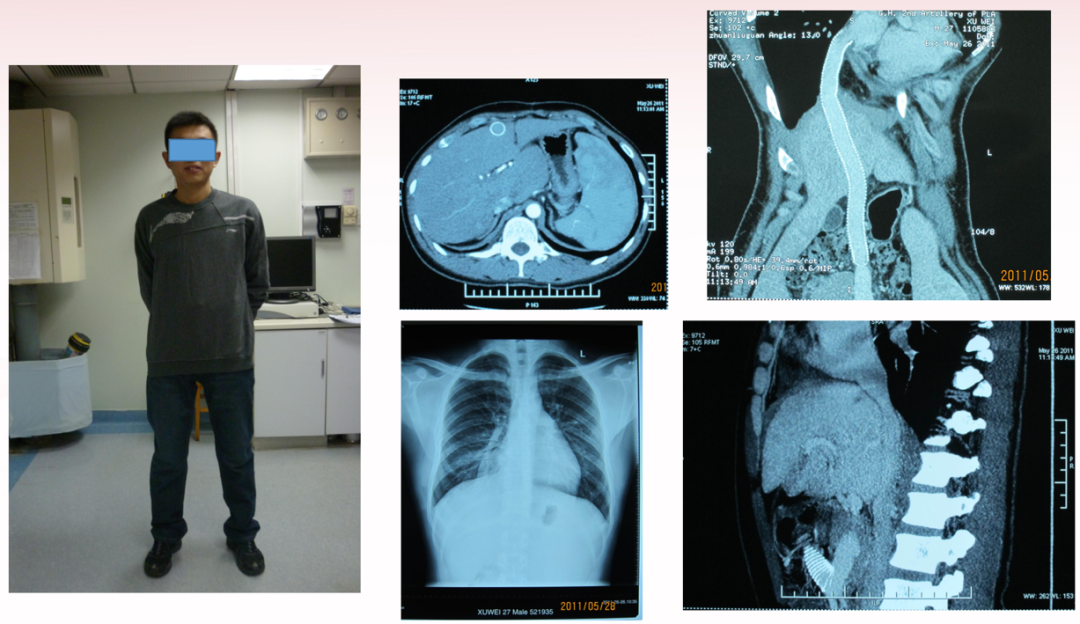

患者,男,28岁,因反复腹胀4年余于2008年7月3日入院:4年前,于当地医院行“下腔静脉支架植入术1个月后,在北京一家医院行肠房人工血管转流术,症状明显缓解。1年半以后,出现大量腹水,并发脐疝。超声示人工血管通畅。服用保肝、利尿药物无效,病情渐重,多次出现肝昏迷。为进一步治疗,来二炮总医院。当时测腹围110cm。

入院行腹膜腔-颈静脉转流泵植入术。腹水减少,腹围在85cm左右。

半年后,转流泵阻塞,腹水增多,再次入院。腹围105cm。

4个月期间,腹水回输43次,每次1000-3000ml.间断补充白蛋白。

白蛋白24.6g/L-----35.1g/L

血色素92g/L-------143g/L

腹围88cm---------92cm